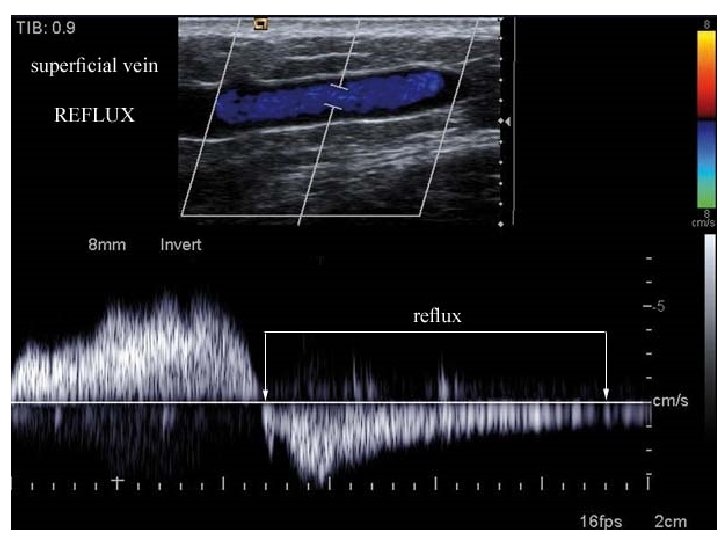

Veins of small and middle caliber • all three layers are discernible but thin • veins of limbs contain valvulae (valves) – duplicature of tunica intima – prevent reverse blood flow (reflux) – insufficiency varix, pl. varices

Venae perforantes Transfascial connections = Perforators • first drawn by Leonardo da Vinci • interconnect deep (80% of blood) and superficial systems • contain valves • insufficient valves → varices • 6 groups according to position

Venae perforantes • simple, double or multiple • run with small artery and cutaneous nerve (Staubesand‘s triad) • 6 groups: foot, ankle, leg, knee, thigh, buttocks • eponyms: Cockett, Boyd, Dodd • e. g. : venae perforantes cruris posteriores tibiales = Cockett‘s perforators – interconnect v. s. m. accessoria posterior and venae tibiales posteriores – 18. 5, 13. 5 a 7 cm proximal to sole 4 -mm tibial perforator

Varices • change of blood flow direction venous hypertension ischaemia

Veins of LL – clinical relevance • • chronic venous insufficiency superficial thrombophlebitis deep venous thrombosis – thrombembolic disease varices – primary (collagen disorder), secondary – treatment: phlebectomy (stripping) + crossectomy, miniinvasive operation (CHIVA – La Cure Hémodynamique de l'Insuffisance Veineuse en Ambulatoire), endovenous laser (EVLT), sclerotization, radiofrequency endoluminal ablation • venous leg ulcer • lung embolia